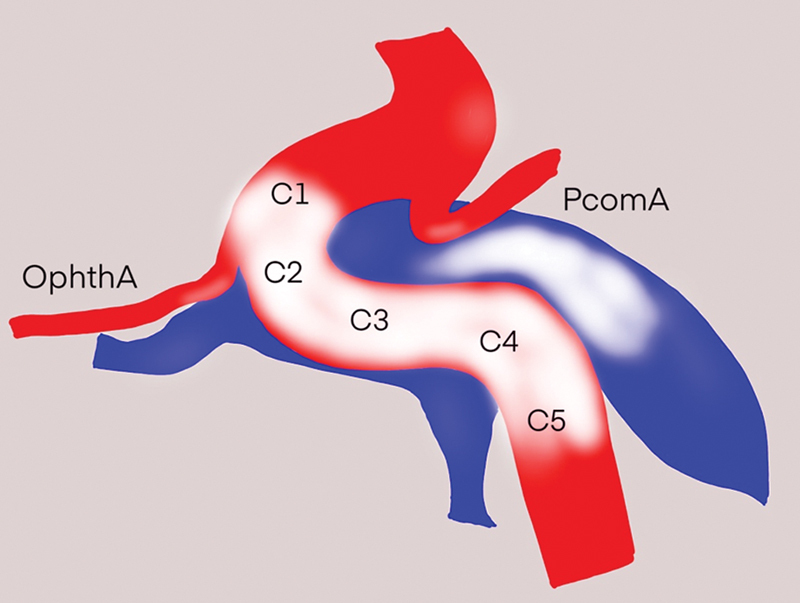

Objectives  This article evaluates the outcomes and efficacy of detachable balloon embolization by single balloon delivery catheter, while identifying factors associated with successful embolization in traumatic carotid cavernous fistula (TCCF) patients. Materials and Methods  We retrospectively collected data of TCCF patients who underwent detachable balloon embolization during March 2020 to April 2024. All cases utilized a single balloon delivery catheter for detachable balloon deployment (GOLDBAL, BALT Extrusion, France). We analyzed demographic, clinical, imaging, and angiographic data, including outcomes, complications, and factors associated with successful embolization. Results  Thirty patients were treated with detachable balloon embolization. The mean age of the patients was 41.1 years (range 17-65 years). The median duration of symptom was 2.0 months (range 0.25-60 months). The most common mechanism of injury is motorcycle accident (83.3%). Nearly all patients had eye redness and proptosis. Angiographic data indicated 29 patients (96.7%) had drainage to the inferior petrosal sinus, 28 (93.3%) had drainage to the superior ophthalmic vein, and 8 (26.7%) had drainage to the superior petrosal sinus. Five cases (16.7%) were classified as small-sized fistula, 19 (63.3%) as medium-sized, and 6 (20%) as large-sized. Regarding the location of the fistula, 8 cases (26.7%) were found in the horizontal segment, while 22 cases (73.3%) were located in the ascending or genu segment of the cavernous internal carotid artery (ICA). Among the 24 patients (80%) who underwent successful embolization, the ICA was preserved in 23 out of 24 patients (95.8%). The remaining patient had ICA occlusion but exhibited no clinical symptoms. Residual cavernous aneurysm was found in two patients, one patient had persistent cranial nerve deficit, while the other was asymptomatic. Statistical analysis demonstrated a significant difference was associated with the fistula location at the ascending or genu segment of the cavernous ICA in relation to successful embolization Conclusion  Despite the availability of several endovascular treatment options for TCCF, using detachable balloon embolization is a relatively straightforward procedure. When combined with a thorough understanding of cavernous sinus anatomy, this approach can significantly enhance the occlusion rate and preserve ICA patency while minimizing complications, particularly when the fistula is located at the ascending or genu segment of the cavernous ICA.